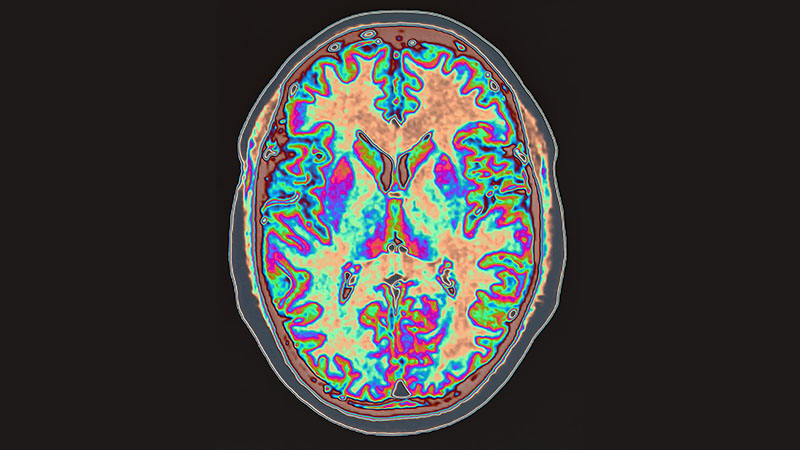

When the Immune System Attacks the Brain

What Is Autoimmune Encephalitis?

Your immune system protects you. It detects germs that could make you sick and attacks them with antibodies. In autoimmune diseases, your immune system attacks a part of your body by mistake. In rheumatoid arthritis, the immune system attacks the joints. In inflammatory bowel disease, the immune system attacks the gastrointestinal tract. In autoimmune encephalitis (AE), the immune system attacks the brain.